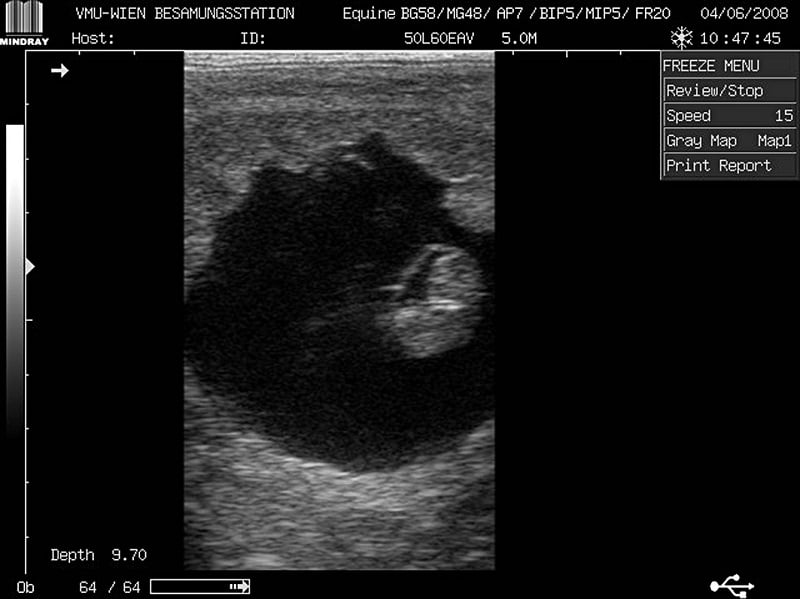

Embryo_aurich[1]